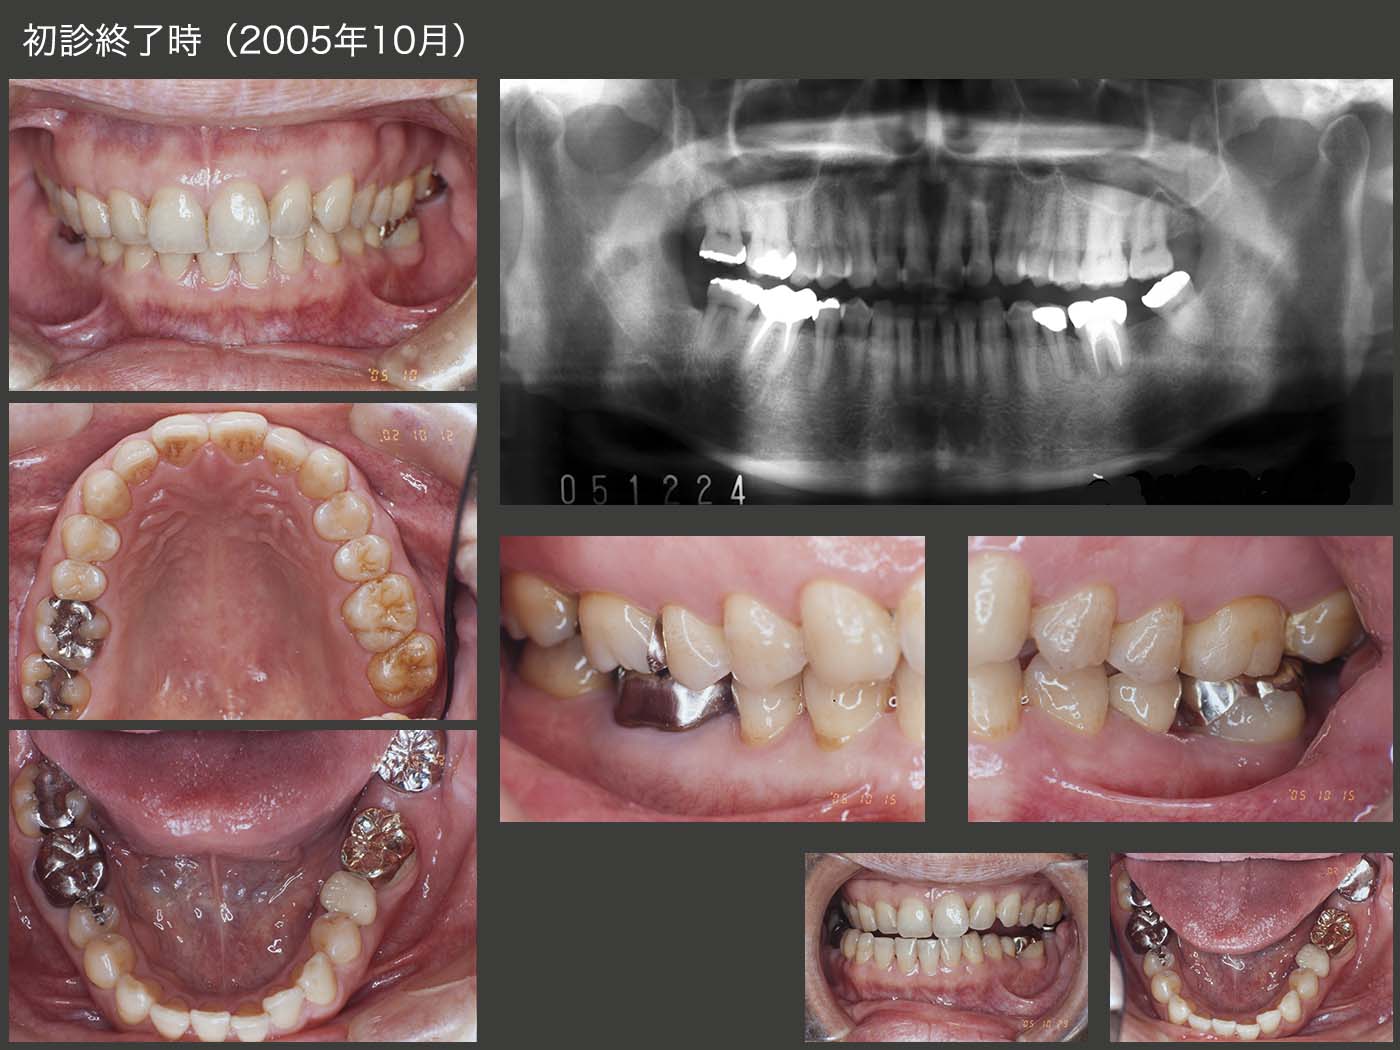

2005年10月,初診終了時の状態.清掃性の観点から,左下にもう一度固定式のブリッジを装着するつもりはないが,左下7部のスペースが気になるかを調べるために,暫間被覆冠で暫く経過を観察した.その結果,まったく気にならないとの回答を得た.左下8にクラウンを装着したが,右側方運動時に咬頭干渉が生じた.口腔内にて調整したために,咬合面形態が悪くなってしまった